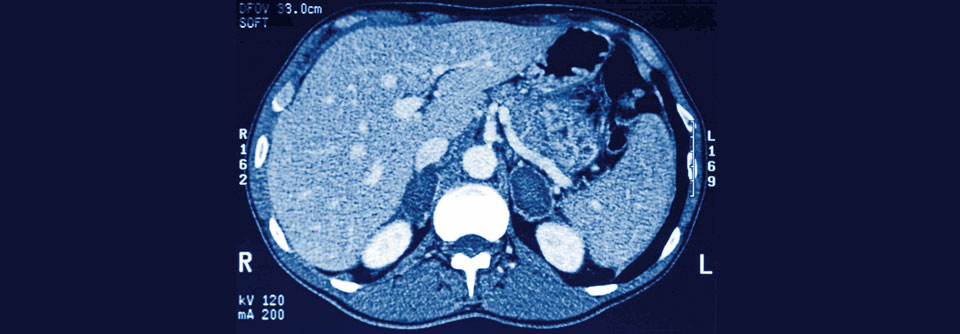

Benigne, aber problematisch: Diese Adenome bildeten Kortisol im Übermaß. Der Patient litt unter einem Cushing-Syndrom. Benigne, aber problematisch: Diese Adenome bildeten Kortisol im Übermaß. Der Patient litt unter einem Cushing-Syndrom. © Science Photo Library/CNRI

Raumforderungen in den Nebennieren entdeckt man meist als Zufallsbefund. Ob der Tumor heraus operiert werden muss, sollte interdisziplinär diskutiert und entschieden werden.